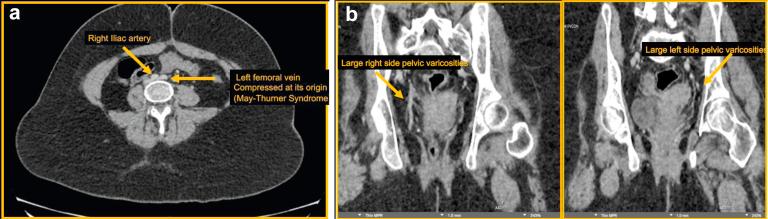

May-Thurner syndrome (MTS) refers to compression of the left common iliac vein (CIV) by the common iliac artery. Although this is typically manifested as acute left lower extremity deep venous thrombosis, MTS is a rare cause of pelvic congestion syndrome. A 17-year-old girl presented with a 5-year history of worsening painful vulvar and labial varicosities. Venography demonstrated pelvic collateralization and left CIV stenosis consistent with MTS. The left CIV was stented with complete radiographic resolution. At 1-year follow-up, the patient is asymptomatic with a widely patent stent. This case highlights the role of endovascular therapy for patients presenting with MTS causing pelvic congestion syndrome.

梅-图二氏综合征(MTS)是指左髂总静脉(CIV)受到髂总动脉的压迫。尽管这通常表现为急性左下肢深静脉血栓形成,但MTS是盆腔充血综合征的罕见病因。一名17岁女孩有5年逐渐加重的外阴和阴唇静脉曲张伴疼痛病史。静脉造影显示盆腔侧支循环形成以及与MTS相符的左CIV狭窄。对左CIV进行了支架置入术,放射影像学显示完全缓解。在1年的随访中,患者无症状,支架通畅。该病例突出了血管内治疗在因MTS导致盆腔充血综合征患者中的作用。